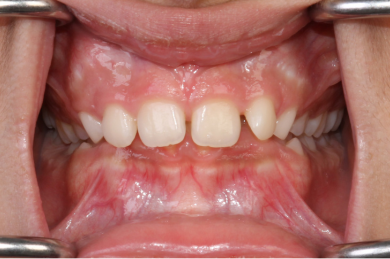

ارتودنسی یک علم دندانپزشکی است که بر روی اصلاح رابطه فکی و صاف کردن دندان های شما متمرکز است. کلمه ارتودنسی ریشه در زبان یونانی دارد. orthos  به معنای صاف و odons به معنای دندان است. ارتودنسی به طور خاص به تشخیص و درمان ناهماهنگی و بی نظمی دندان و فک می پردازد. اگر دندان‌های کج، روی هم و نامرتب دارید یا رابطه فکی شما درست نیست ممکن است نیاز به مراجعه به دندانپزشک ارتودنسی داشته باشید.

هدف از درمان ارتودنسی یک رابطه صحیح فکی است. رابطه فکی درست به معنای دندان‌های صافی است که به خوبی با دندان‌های فک مقابل به هم متصل و جفت می‌شوند. این کار گاز گرفتن، جویدن و صحبت کردن را برای شما آسان تر می کند. تمیز کردن راحت تر، بهداشت دهان و دندان بهتر، گفتار واضح تر، لبخند زیبا تر، جلوگیری از پوسیدگی ، بیماری لثه و سایش بیش از حد دندانها همگی از مزایای آن است.

-  دیپبایت، زمانی که دندان های بالایی روی دندان های پایینی شما را زیاد می پوشاند که  این امر معمولا موجب سایش دندانها میشود و حتما باید درمان شود.

-  اپن بایت، زمانی که دندانهای جلویی فک بالا و پایین هیچ همپوشانی ندارند و بین آنها فاصله است. معمولا بیماران اپن بایت با مشکل گاز گرفتن میوه ها و خوراکیها مواجه هستند.

-  دندان ها روی هم قرار گرفته اند کج و نامرتب هستند. . زمانی رخ می دهد که فضای کافی برای رشد و نمو طبیعی دندان های دائمی وجود نداشته باشد.